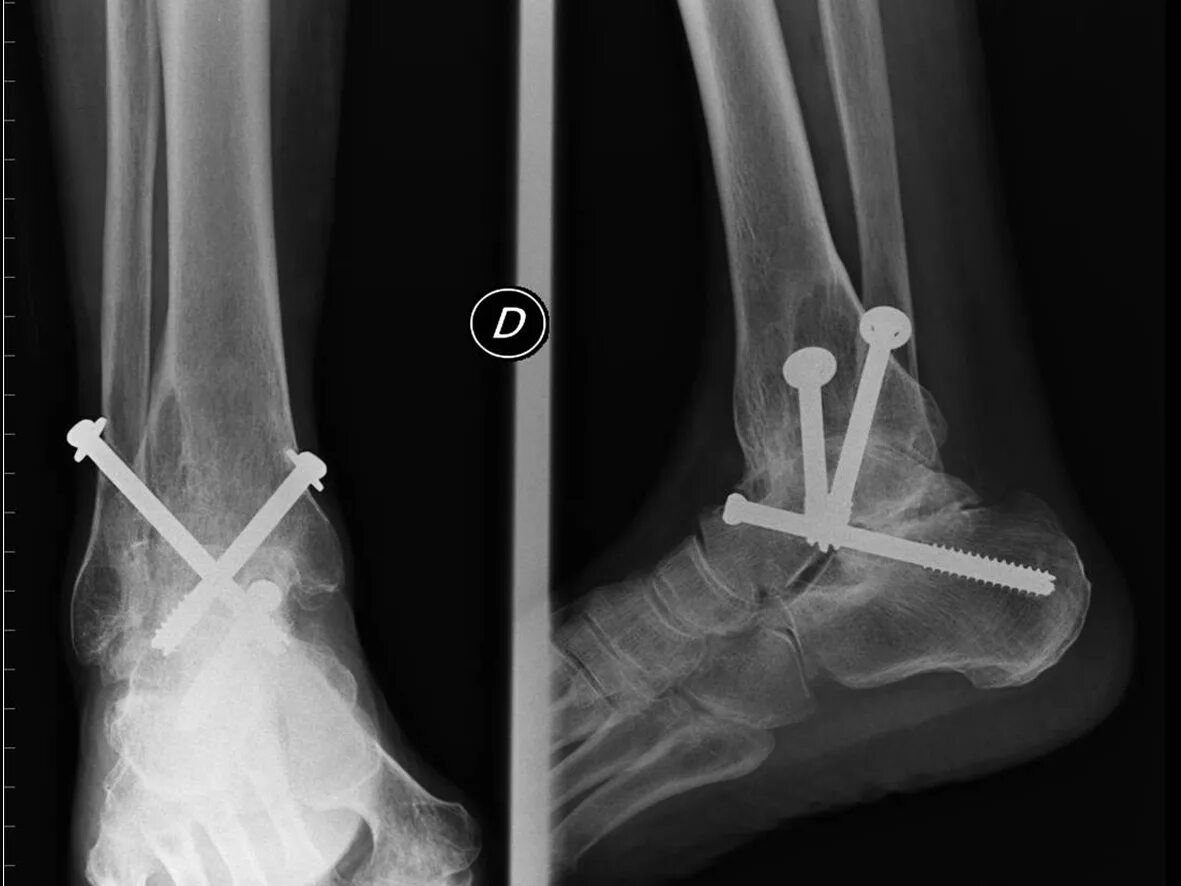

Артродез форум